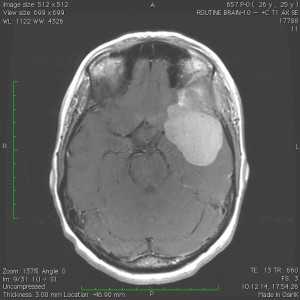

Пациентка В., 25 лет. В возрасте 9 лет перенесла острый лимфобластный лейкоз, по поводу чего проводилась лучевая терапия.

За 2 месяца до поступления в стационар появилась боль в левой височной области, левом глазном яблоке, слезотечение. Консультирована офтальмологом — выявлено высотные левого глазного яблока на 6 мм, по сравнению с правом глазным яблоком, а также признаки внутричерепной гипертензии в виде застойных дисков зрительных нервов. При МРТ выявлена больших размером внемозговая опухоль средней черепной ямки с гиперостозом и распространением в глазницу слева.